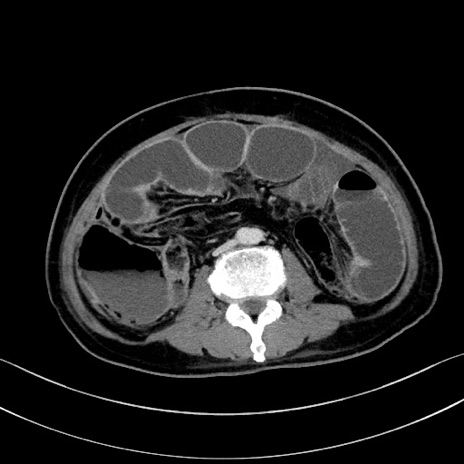

症例28(横断像)

【症例】60歳代男性

【主訴】嘔吐

【現病歴】胃癌にて胃全摘後。食思不振が悪化し、夜中に嘔吐することがある。

【既往歴】胃癌、胃全摘、脾摘、胆摘後

【データ】WBC 5900、CRP 10.56